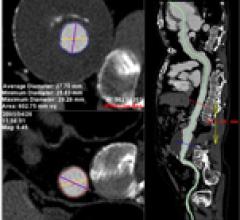

Automated contrast media injectors are used in cardiac imaging to help improve patient safety and enhance image quality. These devices can control contrast dosage, record the amount used, speed injections to keep up with faster computed tomography (CT) scanners, and warn clinicians of potential hazards, such as air embolisms or extravasations.